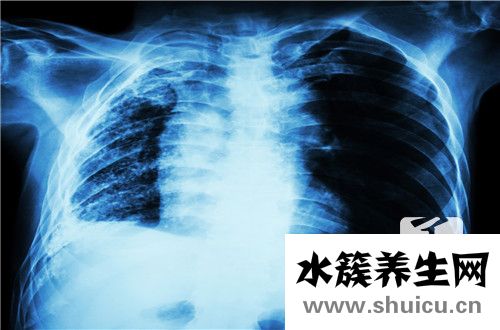

?肺纖維化是指由人類肺部感染的愈合引起的纖維化病變。 它由人肺中的肺間質(zhì)蛋白組成。 肺纖維化的主要原因是由于肺炎或由肺泡炎引起,很容易引起干咳或咳嗽等現(xiàn)象,需要及時治療。

所謂肺部纖維灶,常為肺部感染后,自然愈合后遺留的纖維化病灶。肺間質(zhì)組織由膠原蛋白、彈性素及蛋白醣類構(gòu)成,當纖維母細胞受到化學性或物理性傷害時,會 分泌膠原蛋白進行肺間質(zhì)組織的修補,進而造成肺臟纖維化;即肺臟受到傷害后,人體修復產(chǎn)生的結(jié)果。常見的原因是肺結(jié)核已經(jīng)痊愈或其它的損傷后修復的表現(xiàn)。如果纖維化范圍小,對身體基本不影響,如果范圍廣,就可能導致肺功能降低,出現(xiàn)缺氧和呼吸困難等。

正常肺間質(zhì)由少量的間質(zhì)巨噬細胞,成纖維細胞,肌成纖維細胞以及肺基質(zhì),膠原,大分子物質(zhì),非膠原蛋白等組成。當肺間質(zhì)發(fā)生病變時,上述成分的數(shù)量和性質(zhì) 都會發(fā)生改變。表現(xiàn)為明顯的炎癥侵犯肺泡壁和鄰近的肺泡壁腔,Ⅱ型肺泡上皮細胞替代Ⅰ型肺泡上皮細胞,肺泡間隔明顯增厚以及肺纖維化,最后肺毛細血管喪 失。

肺纖維灶形成的病因機制主要為:早期出現(xiàn)肺泡炎,肺泡內(nèi)有漿液和細胞成分,肺間質(zhì)內(nèi)有大量單核細胞,部分淋巴細胞,漿細胞,肺泡巨噬細胞等炎性細胞浸潤, 肺泡結(jié)構(gòu)完整。進入晚期,慢性炎癥已減輕,肺泡結(jié)構(gòu)為堅實的膠原代替,肺泡壁被破壞,形成擴張的蜂窩肺。膠原、細胞外基質(zhì)、成纖維細胞分布在間質(zhì)中,肺泡 上皮化生為鱗狀上皮。基于以上病理變化,臨床上多表現(xiàn)為進行性呼吸困難或伴有刺激性干咳,胸部X線顯示兩中下肺野網(wǎng)狀陰影,肺功能為限制性通氣功能障礙。 病情呈持續(xù)性進展,最終因呼吸衰竭而死亡。